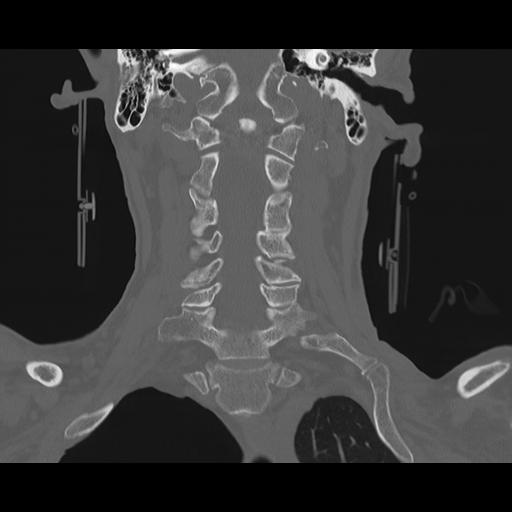

16 HUESO,,Coronal,2.000,HUESO,Coronal,